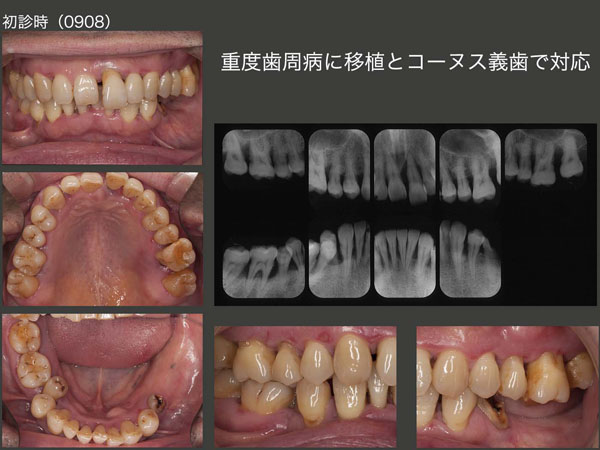

2009年8月初診,59歳男性.全顎的に歯ぐきが痛い,特に右下臼歯が痛くて嚙めないが主訴.左下は12年前に義歯を作り,2年間使用したが,左下5が欠けてからは使ってない.時間がかかってもよいので,できるだけ歯を保存したいとのこと.とても熱心にブラッシングをされる方.

歯周基本治療を行ったのち,右側(右下6,7および右上7)および左上1を抜髄し,自然挺出を期待した.スライドは2010年3月,右下6の抜髄終了時の状態で,すでに挺出を開始していた左上1はかなり挺出してきている.

左右両側ともに小臼歯までの咬合となり,なおかつ右下5が舌側に転位しており,咀嚼できるところが少ない.まず左側大臼歯部の咬合が必要と考え,10年5月に右下5を左下7部へ移植した.

その後,全顎的に歯周外科処置を行った.歯周ポケットが改善できなかった左上6の口蓋根は抜根した.保存できた頰側根は,頰側に位置していたので,咬合できるところまで移動させた.左上1は動揺等が改善できず,抜歯となった.